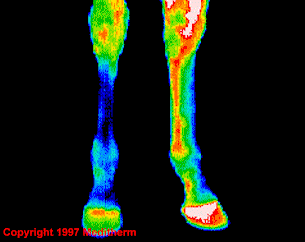

Termograma în infraroșu

Proces inflamator picior stânga spate